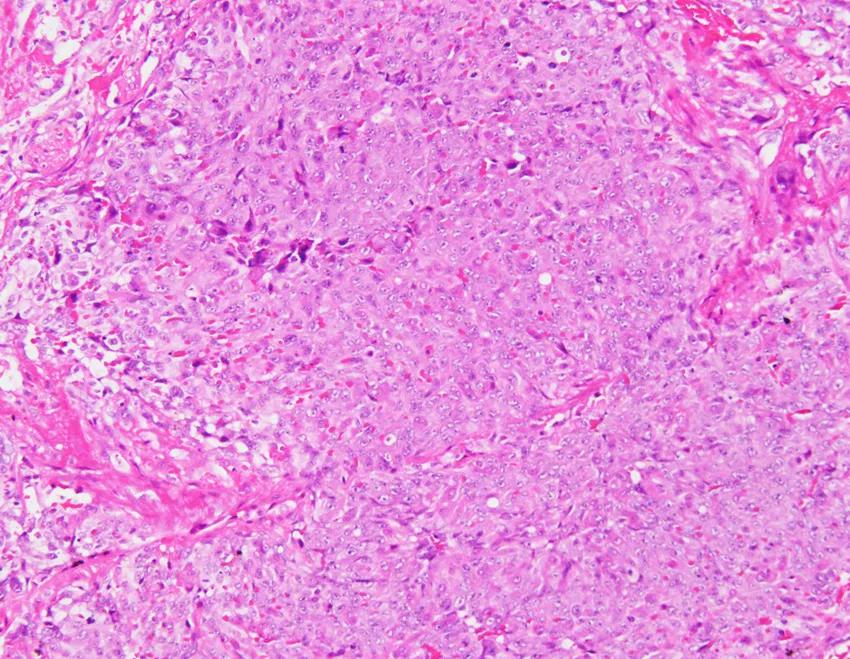

活检病理:

A 术中可见肺组织表现有弥漫性出血性病灶;B 低倍镜下病理病灶;C 高倍镜下可见大量梭形细胞;D 免疫组化可见CD34(+)、CD31(+)

术后病理:血管肉瘤

王岩主任(病理科)点评:

送检楔形切除肺组织一块,大体可以看到肺组织切面有凝血,并有大小不等的多枚结节。

镜下可以看到肺泡腔的弥漫出血,局部可以看到较多官腔样结构,衬覆上皮有异性性,另外可以看到成片的异性细胞在肺内多结节生长,呈梭形,可见到多量核分裂,这时候倾向为高度恶性肿瘤病变,镜下表现可排除上皮样血管内皮瘤,因为后者呈低度恶性、轻度异型性、核分裂相不如该患者明显。该患者组织学表现在病理上有以下考虑:肺腺癌?恶性间皮瘤?恶性黑色素瘤?血管肉瘤?硬化性肺细胞瘤?借助免疫组化结果CK(-)、TTF-1(-)Ki67(70%+)可以排除上皮样血管内皮瘤、肺腺癌、恶性间皮瘤、硬化性肺细胞瘤。HMB45(-)、melan- A(-)排除恶黑肺转移可能性。CD31(+)ERG(+)支持血管肉瘤的病理诊断。